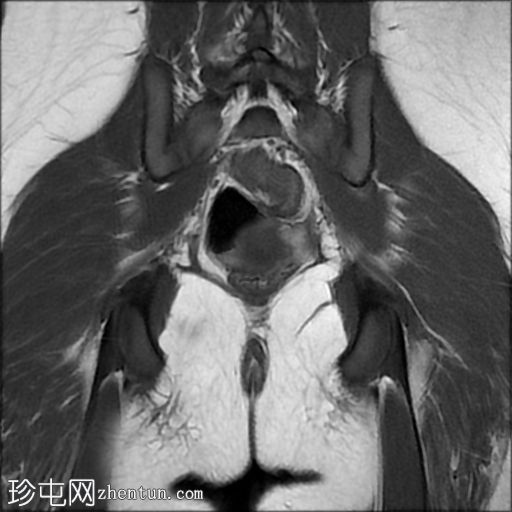

冠状面

T2

子宫体相对较小,发育良好。宫颈发育不全。

阴道整体不显影,远端可见一层细小的纤维组织,在轴向和矢状面T2加权序列上最为明显。

随后,子宫内膜和宫颈腔扩张,出现混合液体/血液降解信号(积血)。它诱发中至高T1信号,伴有依赖性低信号碎片,无病理性强化。

周围轻度盆腔积液,盆腔及附件脂肪平面模糊,信号相似,增强后强化明显。这些发现提示可能有渗漏液/血液积聚,并伴有腹膜反应。

右侧附件卵巢功能性囊肿。